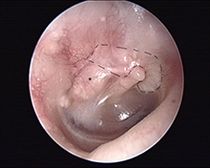

Subtotaler Trommelfelldefekt (rechtes Ohr)